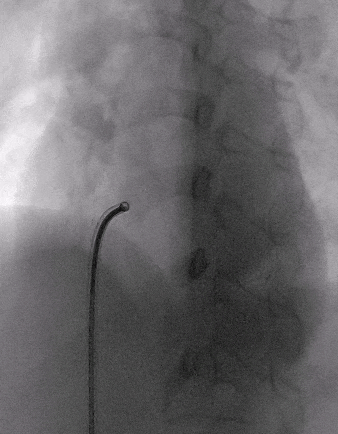

术前造影:室间隔缺损处造影,造影显示有膜部瘤形成,测量缺损大小,左侧基底大小10.8mm,右侧分流口2处,分流大小约2mm。

室间隔缺损介入封堵

根据术前测量和术中造影结果,选择MemoSorb全降解封堵器ABFDQ-Ⅱ08,配合8F可降解封堵器介入输送系统进行封堵。

建立输送轨道

飘导丝法导丝过室间隔缺损

圈套器抓捕导丝

送入8F输送鞘

改变输送鞘方向

使输送鞘朝向心尖